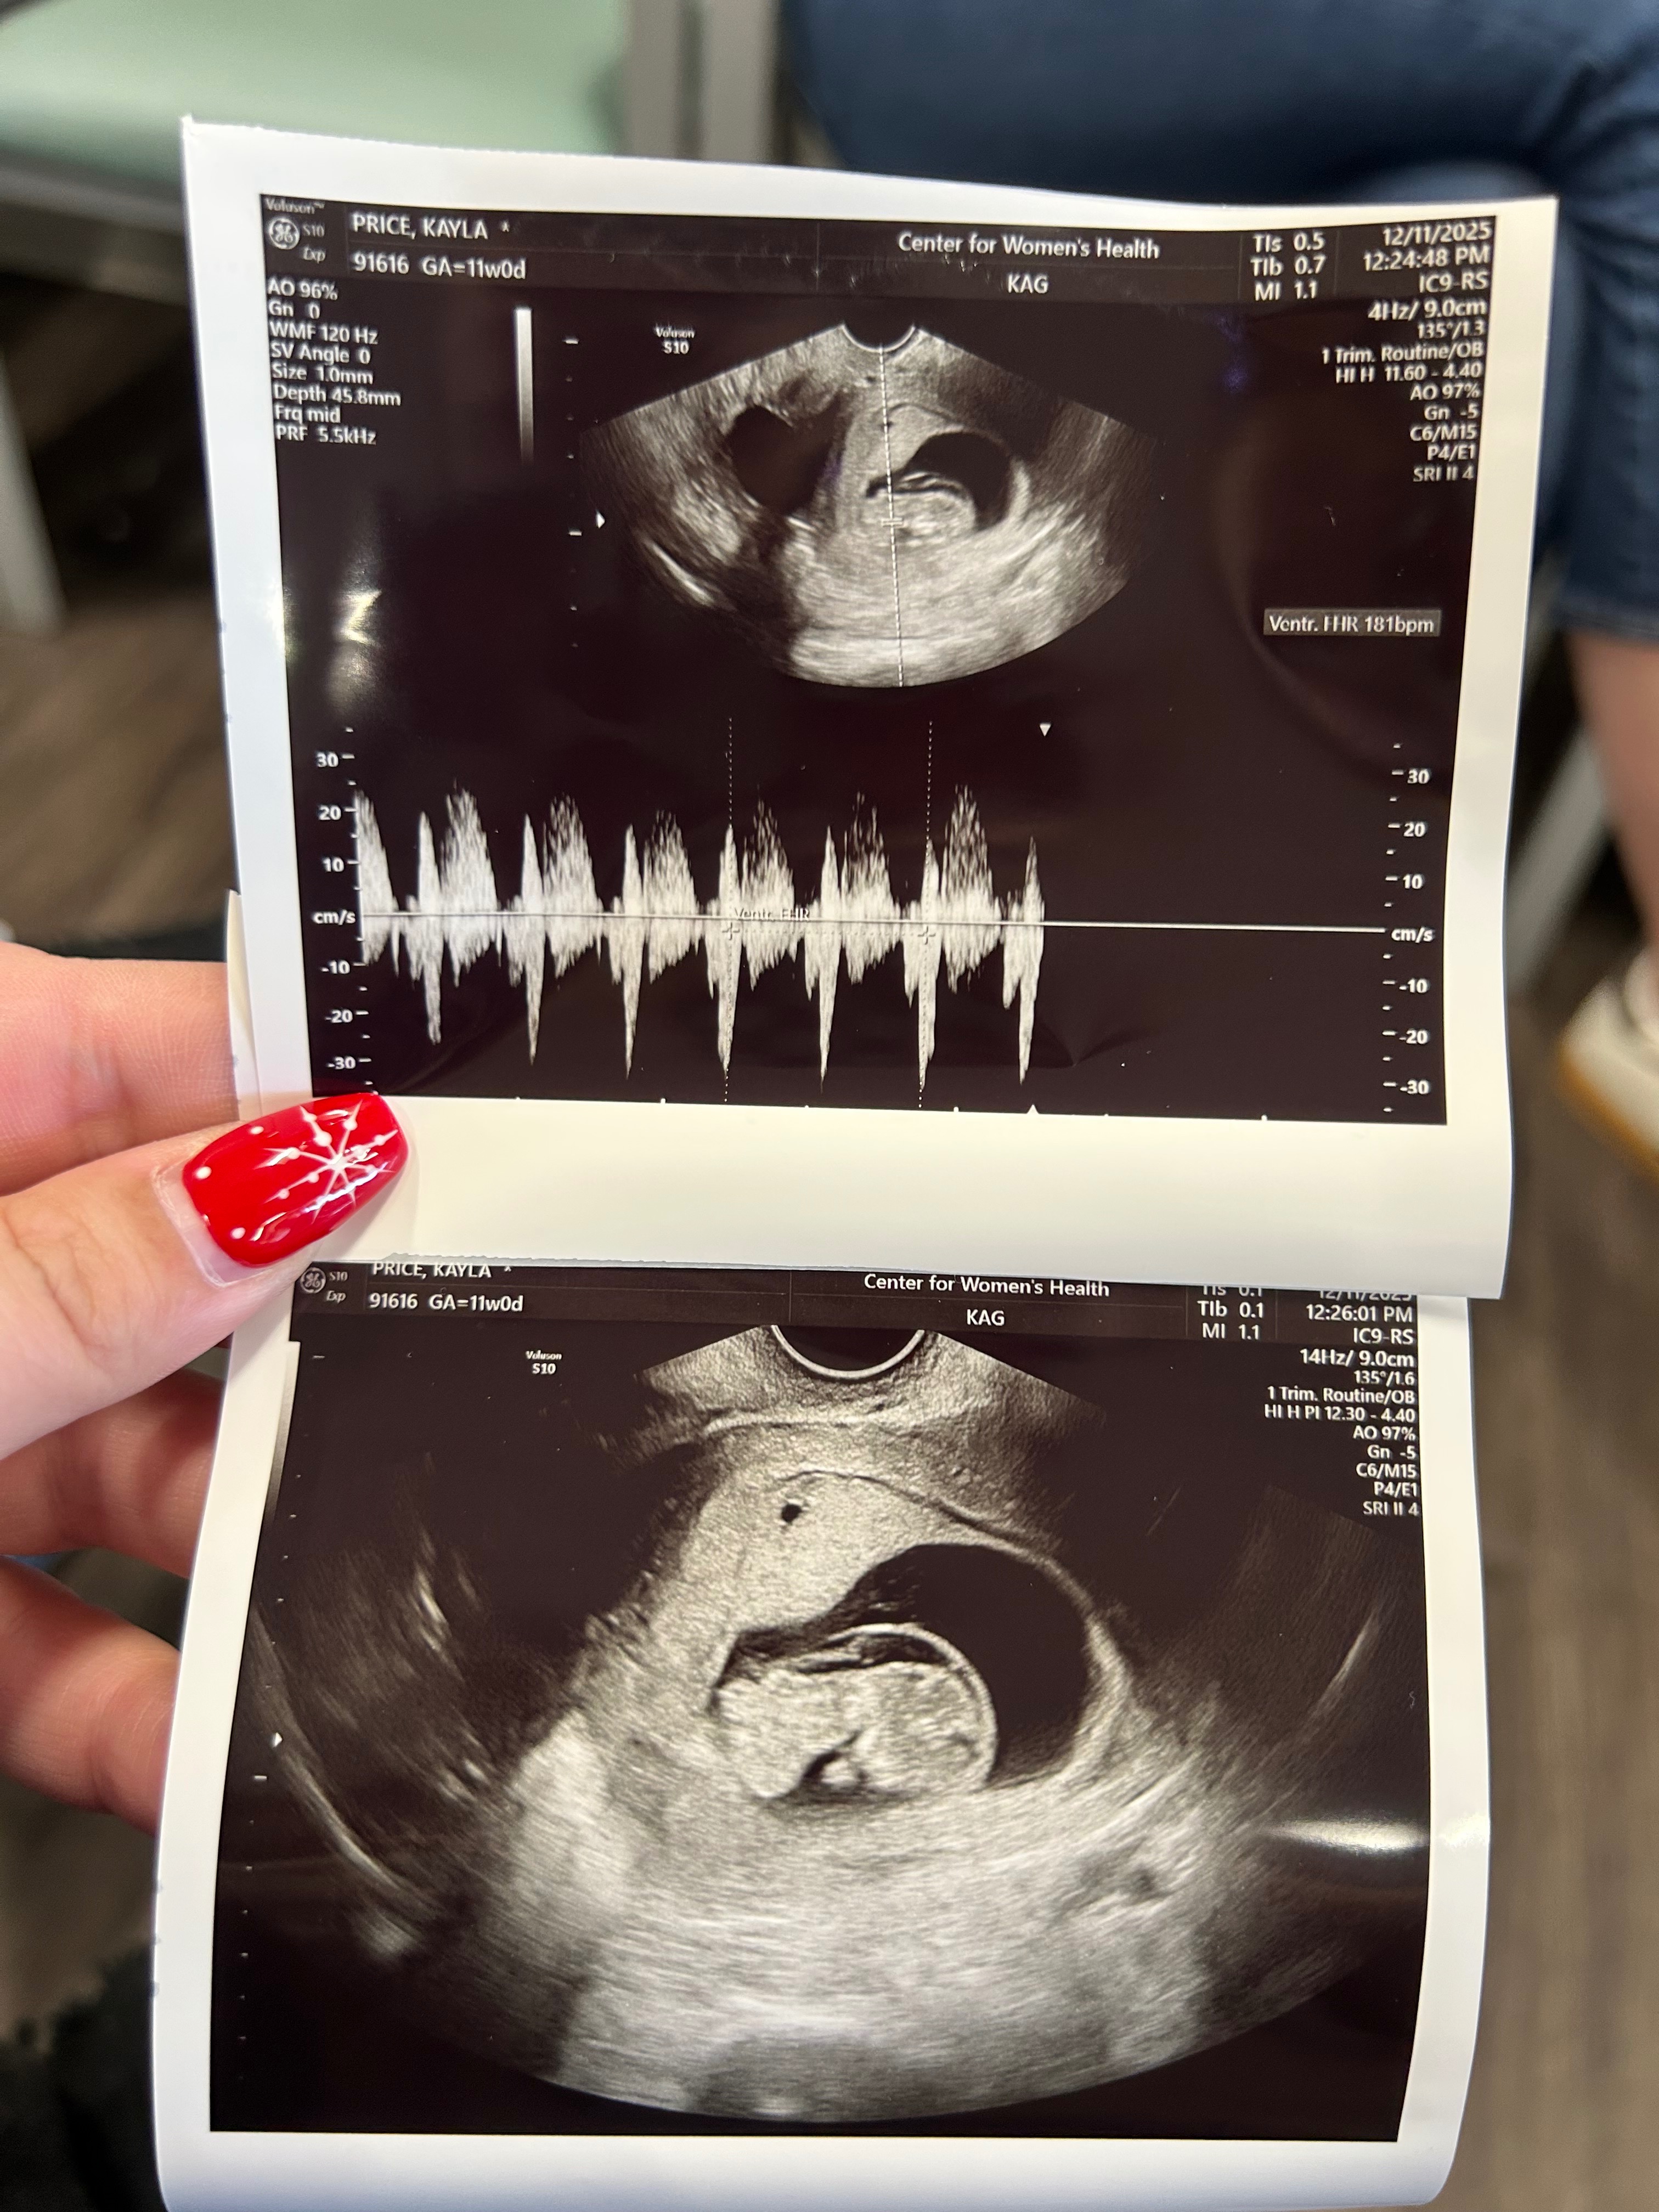

Me and my husband found out we were pregnant on November 2nd. We had an appointment with a high-risk doctor on December 22nd where a possible abdominal issue was found. We then went to our anatomy scan on February 2nd, and the abdominal issue they found at the previous appointment was worse than they originally anticipated. Our little girl was diagnosed with something called Limb-Body Wall Complex(LBWC). It basically means all of her internal organs are outside of her body, including part of her heart. It also can cause spinal issues, and her spine has a lot of curving that is not good. She’s basically twisted and curled up and “stuck” to the placenta wall to where she can’t really grow, and she’s measuring really small. It’s a fatal diagnosis and extremely rare. We have been going to weekly ultrasounds since for a weekly heartbeat check. Whenever we go in and there’s no heartbeat, we will go to labor and delivery and deliver her, unfortunately stillborn. There’s no known cause of this, nothing we did wrong, just a very sad and unfortunate circumstance. Any money donated will go to any hospital bills, time taken off work, a memorial service or cremation(whichever route we decide to go), Please keep us in your prayers over the next few weeks/months as we navigate this unimaginable and very tough time.❤️